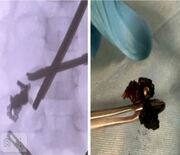

Республикӑн тӗп хулинче арҫынна коронарографи тунӑ, стент вырнаҫтарнӑ.